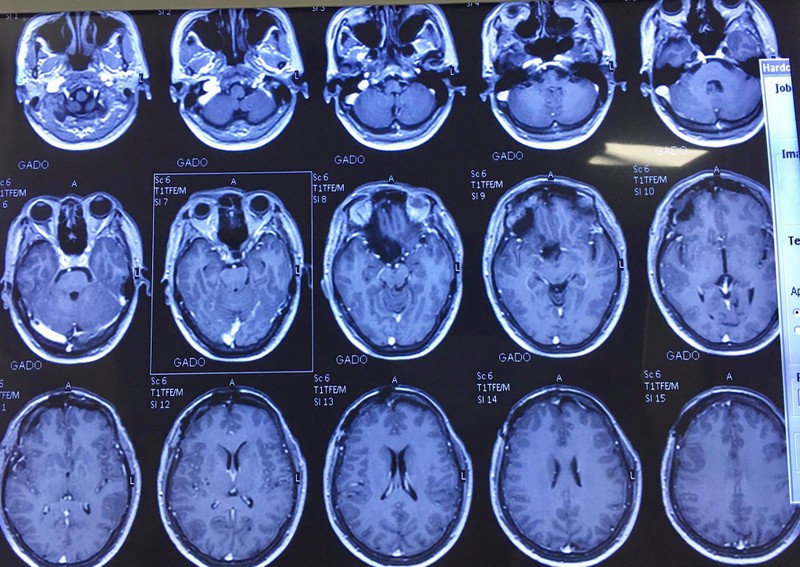

Các bác sĩ của Bệnh viện Hữu nghị Việt Đức đã khám và tiến hành các kỹ thuật cắt lớp vi tính, chụp cộng hưởng từ cho bệnh nhân và chẩn đoán bệnh nhân bị u màng não vùng trên yên. Khối u đè đẩy tuyến yên và giao thoa thị giác xuống dưới, ôm quanh động mạch não giữa bên phải và 2/3 chu vi động mạch cảnh trong hai bên, ôm toàn bộ dây thần kinh thị giác phải, tiếp xúc dây thần kinh thị giác bên trái.

Phim chụp của bệnh nhân sau phẫu thuật. Ảnh: Bệnh viện Hữu nghị Việt Đức

Sau phẫu thuật, người bệnh hoàn toàn tỉnh tảo, hết u, bảo tồn được toàn bộ cấu trúc dây thần kinh II, cuống tuyến yên, động mạch não.